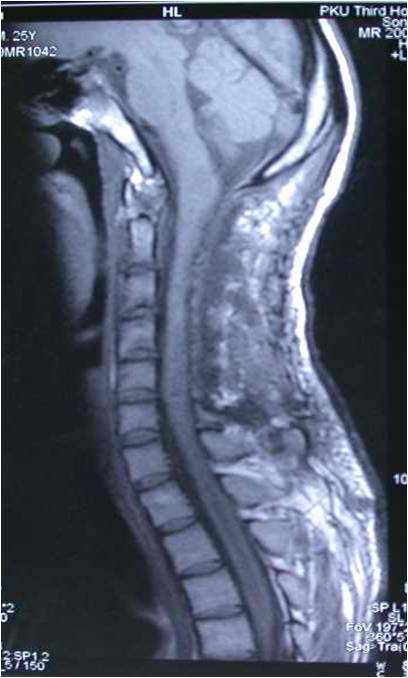

术后MRI见肿瘤切除满意